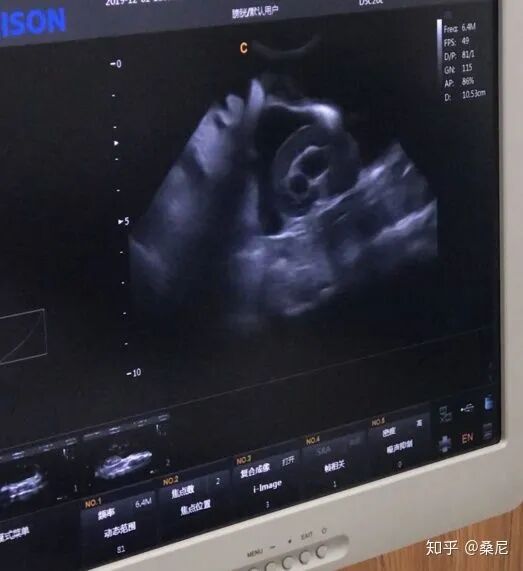

今年 12 月 2 日诊断为高度疑似传腹,12 月 4 日更换宠物医院再次进行全面检查,同时增加了心超这一项。心超结果显示为典型性心脏病,右心房严重肿大、有微弱阴影疑似为肿瘤、腹水很严重。吃喝拉撒正常,精神状态比较萎靡。腹水送检实验室结果显示为阴性,但超声检查显示有髓质罗圈症。元宝的情况属于比较危重的,经过与医生的沟通确定治疗方案,治疗至今猫咪已经基本恢复正常。

元宝更换宠物医院后抽取 5ml 腹水送检,三天得到检查结果显示为阴性。这里要特别说明的是,结合元宝的腹部 B超检查和医生讨论并不能完全排除元宝没有传腹的可能性。